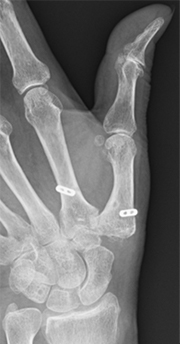

母指CM関節症の診断は問診や身体所見がとても大切です。当院では、問診や身体所見に加えてまず手関節X線撮影を行い関節変形の評価を行います。典型例ではCM関節の隙間が狭くなり、骨棘(こつきょく)の形成やCM関節の亜脱臼を認めます。

母指CM関節の変形、骨棘形成、亜脱臼を認める